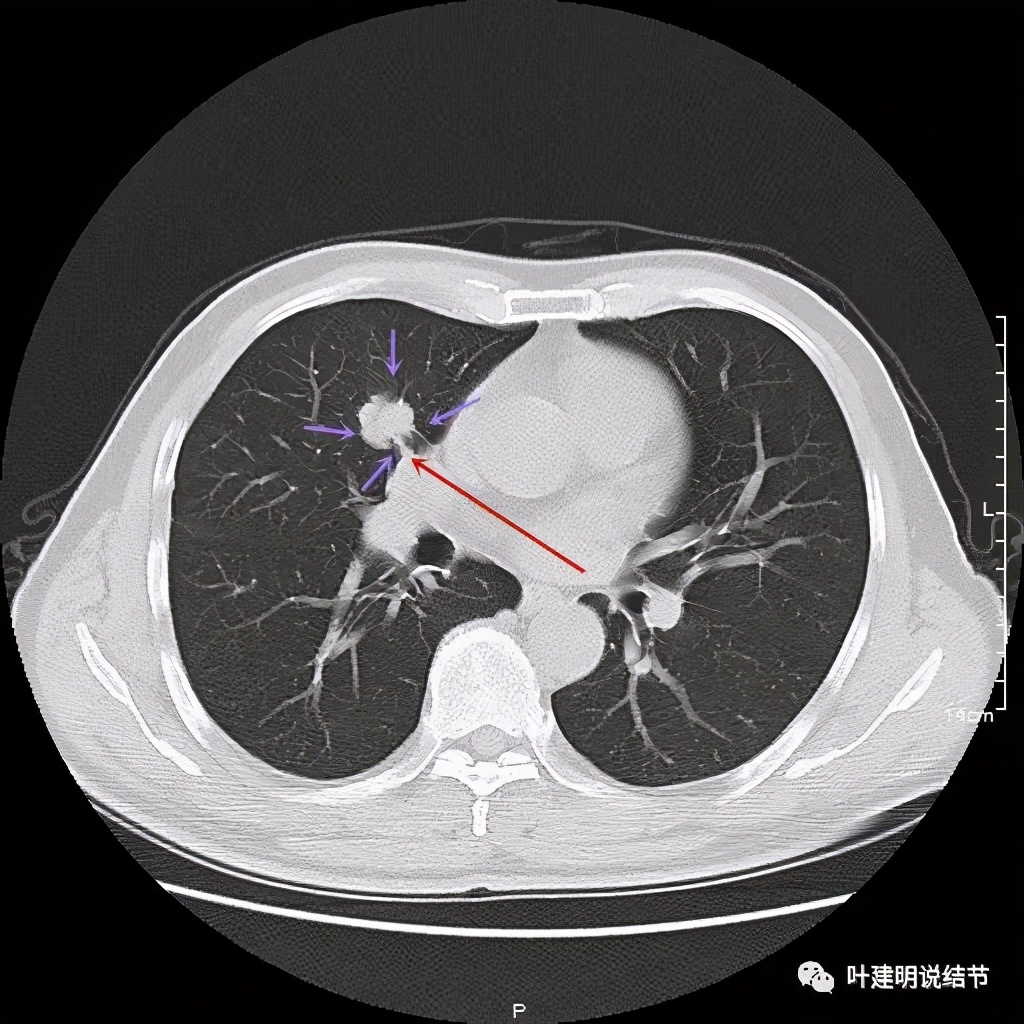

上图示病灶实性,且粉色箭头所示处边缘不平整,似细毛刺征(不太典型),蓝色箭头示像支气管截断(肿瘤堵塞的样子,但后文中有气管镜下未见异常,那么可能是角度的关系)

上图紫色箭头示浅分叶征明显,红色箭头示病灶牵拉胸膜(纵隔侧的胸膜)